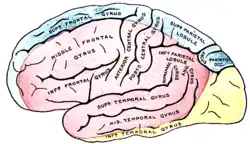

Nach dem Eintritt in den Schädel durch den Canalis caroticus zweigt aus der Arteria carotis interna jeder Seite ein Gefäß zum Auge (Arteria ophthalmica) ab. Nach Abgabe weiterer kleinerer Äste teilt sie sich in die Hauptstämme des vorderen Kreislaufs, die mittlere Hirnarterie (Arteria cerebri media) und die vordere Hirnarterie (Arteria cerebri anterior, bei Tieren als Arteria cerebri rostralis bezeichnet). Erstere versorgt die seitlichen (lateralen), letztere die der Mitte zugewandten (medialen) Teile der jeweiligen Großhirnhemisphäre mit Ausnahme von Teilen des Temporallappens und des gesamten Occipitallappens, die vom hinteren Kreislauf gespeist werden. Die tiefen Kerngebiete (Basalganglien, Thalamus) haben eine gemischte Versorgung. Die beiden vorderen Hirnarterien sind durch die sehr kurze Arteria communicans anterior miteinander verbunden.

Die Wirbelarterien in ihren Endsegmenten und die Arteria basilaris entsenden Äste zum Hirnstamm und Kleinhirn (A. cerebelli inferior posterior, A. cerebelli inferior anterior, A. cerebelli superior). Oberhalb der Brücke teilt sich die Arteria basilaris abermals und wird zu den beiden hinteren Hirnarterien, die sich in die Arteriae occipitales medialis bzw. lateralis teilen und die hinteren Bezirke des Großhirns sowie Teile des Zwischenhirns versorgen. Eine individuell unterschiedlich stark angelegte Arteria communicans posterior verbindet die hintere Hirnarterie jeder Seite mit der inneren Halsschlagader.

Versorgungsgebiete der Großhirnrinde: Arteria cerebri anterior (blau unterlegt) |